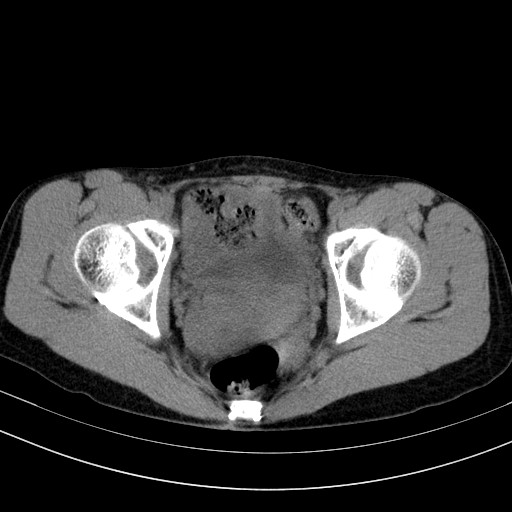

以下是引用随光逐影在2009-4-7 8:17:00的发言:[br]考虑宫颈占位性病变(宫颈癌?);建议行进一步检查。

以下是引用jiangjing在2009-4-7 16:46:00的发言:[br]宫颈增大,结构不清,右侧附件区可疑囊样占位,建议增强及mri 检查